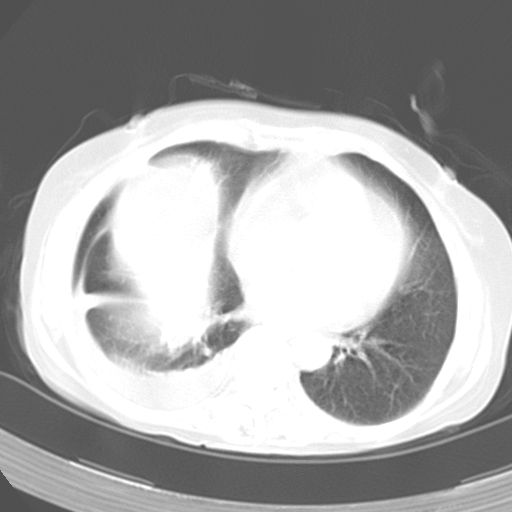

以下是引用dyqct在2006-12-7 21:08:00的发言:[br]考虑:1、肝内外胆管多发性结石伴肝左叶外侧段肝萎缩;[br] 2、右膈下多发脓肿;[br] 3、右侧少量胸腔积液、斜裂积液;[br] 4、左肾囊肿。

以下是引用jiazh在2006-12-7 20:37:00的发言:[br]肝脏周围半狐形低密度影,肝脏表面受压推移,考虑膈下脓肿可能性大;2、右侧胸腔积液

以下是引用拾荒者在2006-12-7 21:44:00的发言:[br]肝内外胆管多发结石,右膈下多发脓肿,右胸膜腔及叶间裂积液,左肾囊肿。[br] [br]